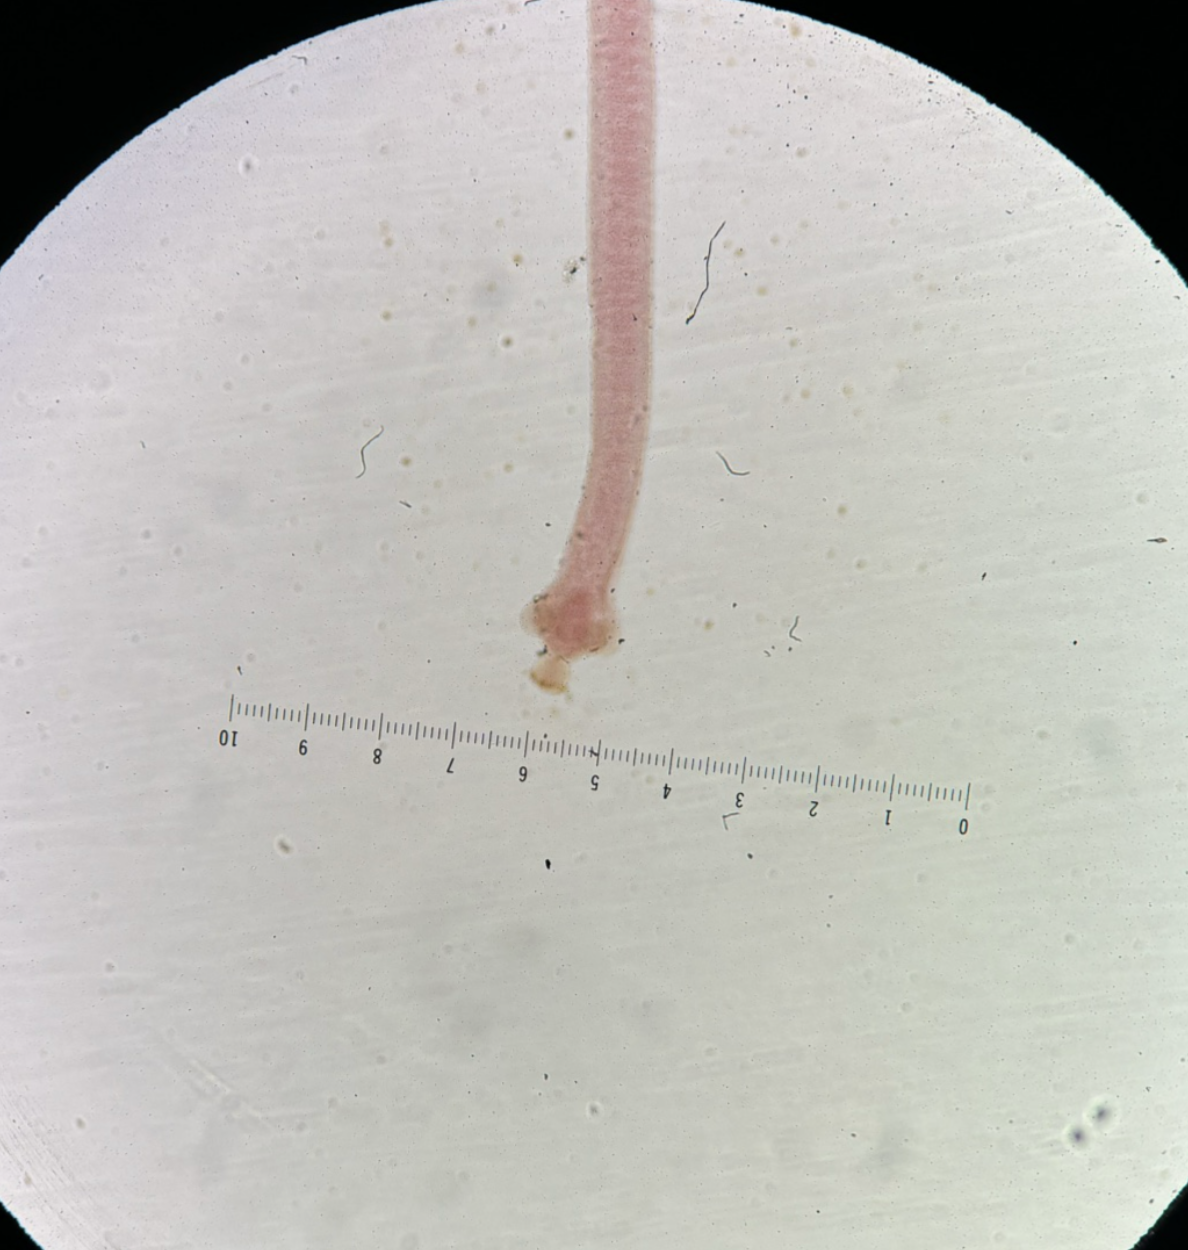

Family: Schistosomatidae

Species/Stage: Schistosoma spp - adult female